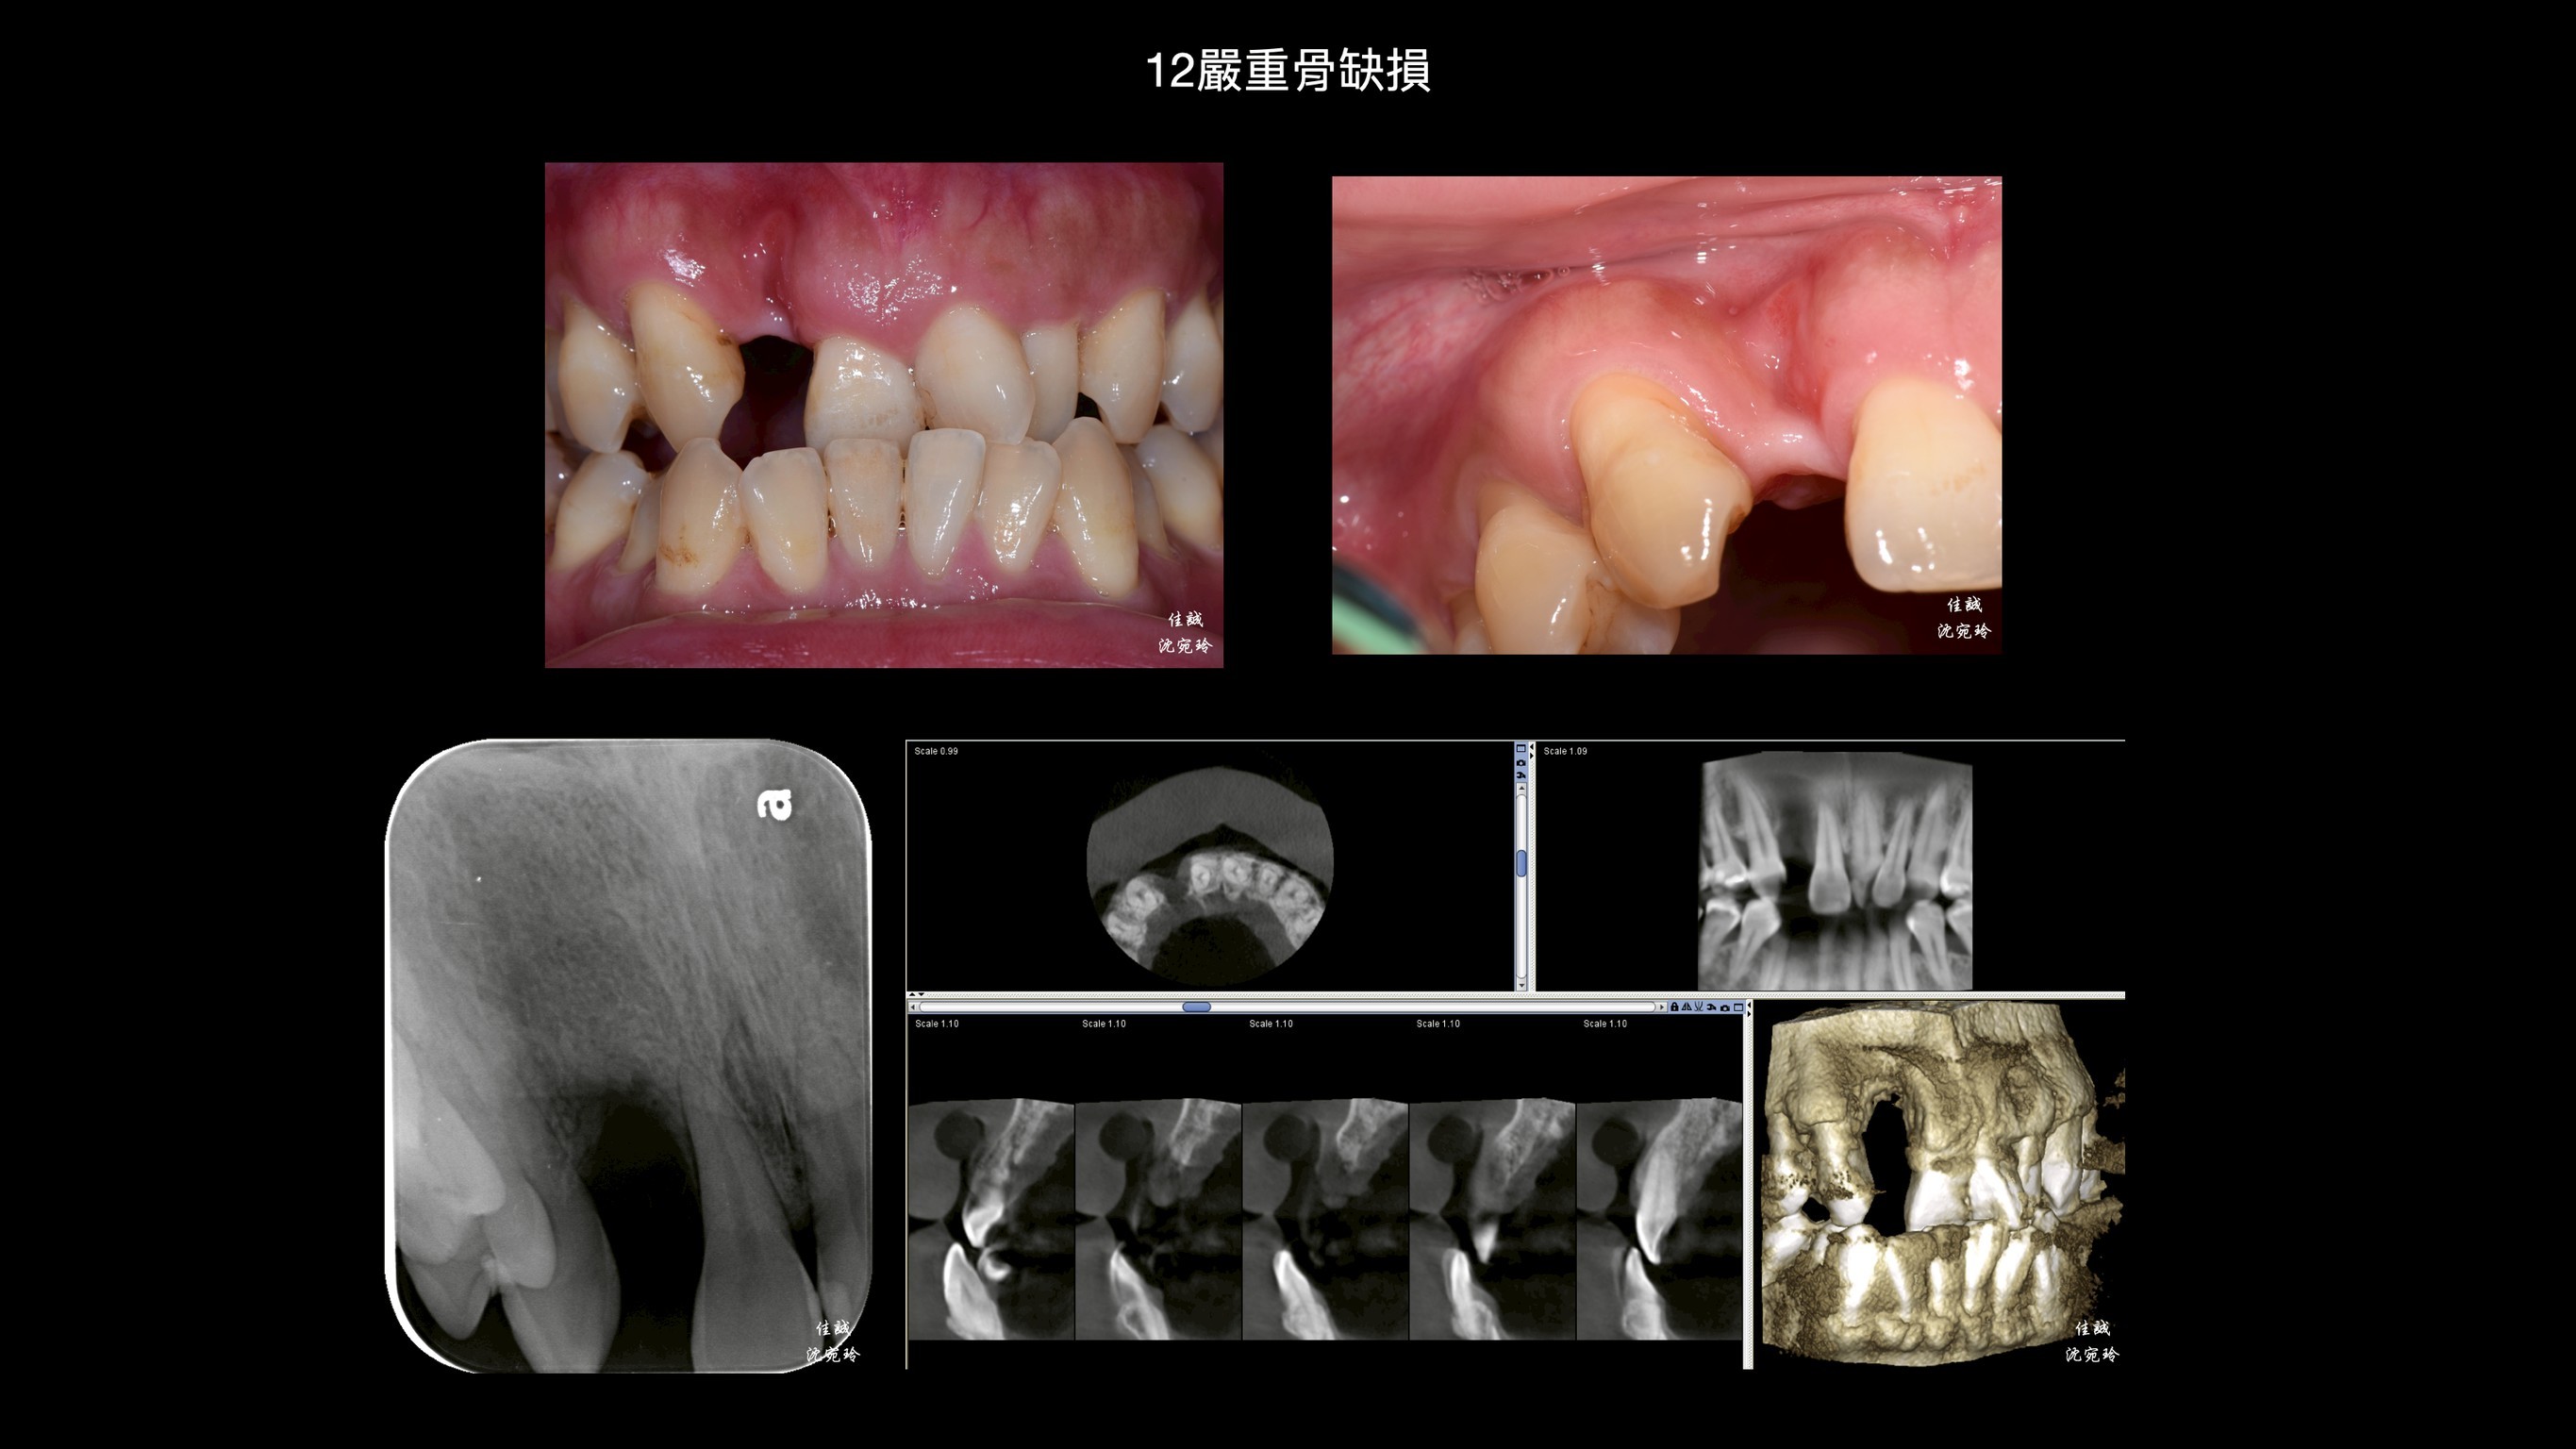

感謝醫師轉診,C先生自述右上側門牙因牙周病太搖而自行掉落,上前來「評估缺牙區可否植牙或是假牙?」

由於骨缺損程度大,此區若直接做假牙除了會塞食物,也不美觀。另外,做牙橋會犧牲太多齒質,需要根管治療;而馬里蘭牙橋做在平行度不佳的前後牙齒上面,也需要修磨較多,使用年限也不高;加上咬合排列不正,建議先做補骨手術,再接著做矯正治療,等矯正完成後,才做植牙或假牙的選擇。

手術挑戰是術區牙齦皮薄、骨缺損大,加上病患希望矯正前只開一次手術,對於方便矯正的接續進行,這次只補FDBA和 OSSIX plus。因為預期將來會吸收一些,我盡量補oversize,最後選在牙齒掉落後的三個月進場,增加贏面。